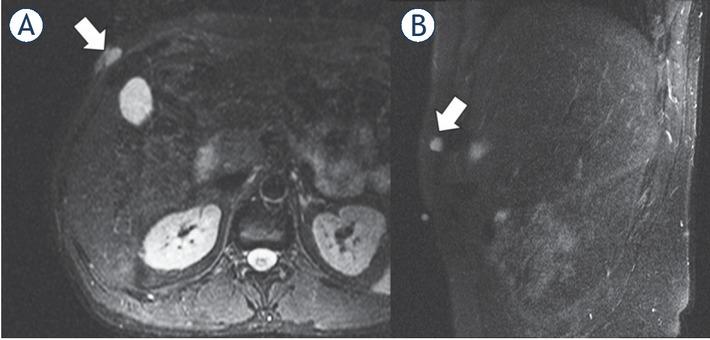

Figure 4